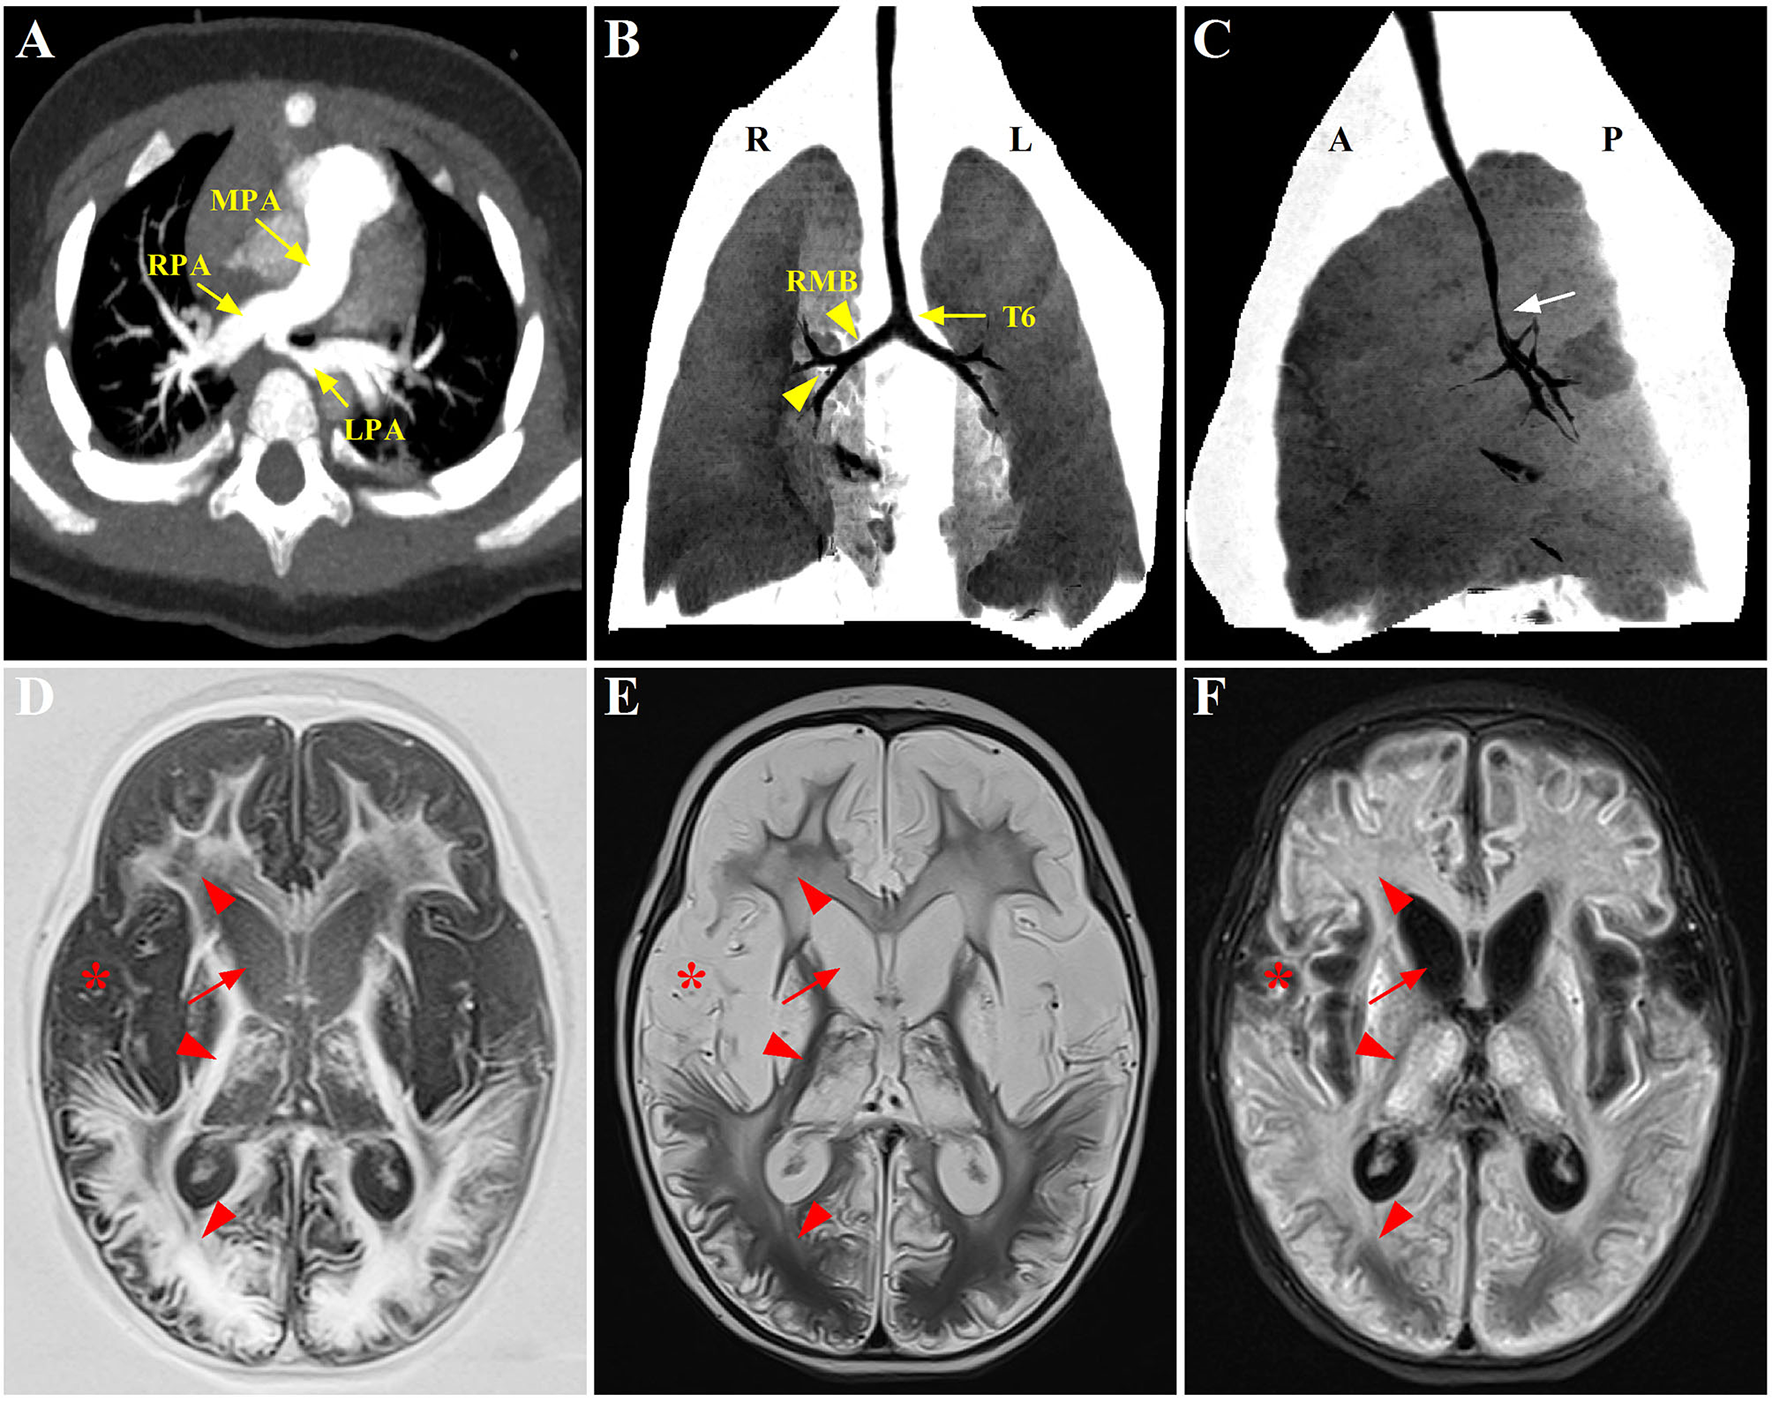

Figure 1

Radiographic evaluation of the PAS, tracheobronchial abnormalities, and neurological lesions through CT and MRI scans. (A) Preoperative CTA showing the anomalous origin of LPA from the posterior aspect of RPA. (B,C) Postoperative three-dimensional reconstruction of CT showing a lower level of bronchial bifurcation at T6 (yellow arrow) and a long RMB with bronchial divisions identical to left bronchial type (yellow arrowhead), associated with a stenotic segment in the distal trachea (white arrow); (D–F) Axial T1-weighted, T2-weighted, and T2-FLAIR brain MRI, respectively, displaying symmetrical signal abnormalities throughout the gray matter, white matter, and deep nuclei (red arrowhead), and extensive cortical necrosis (red asterisk), cerebrum atrophy and ventriculomegaly (red arrow). PAS, pulmonary artery sling; CTA, computed tomography angiography; LPA, left pulmonary artery; RPA, right pulmonary artery; RMB, right main bronchus; FLAIR, fluid attenuated inversion recovery.

Despite being hemodynamically stable under mechanical ventilation, the postoperative course of the patient was complicated with airway obstruction and hypercapnia. Repeat chest CT (three-dimensional reconstruction) on postoperative day 15 showed two bi-lobed lungs and anomalous lateralizing features of the right main bronchus (RMB), characterized by a more horizontal course and a long main bronchus. Additionally, it was noted that the trachea bifurcation occurred more distally at the level of T6 rather than T4-5, with the lumen diameter of 2.0 mm at the most stenotic part of the trachea. Moreover, several consolidative opacities in the inferior lobes of both lungs were found (shown in Figures 1B,C). However, no features of cardiac heterotaxy and spleen anomalies were found in the subsequent ultrasound scan. The patient experienced three unsuccessful extubation within 18 days in one of which cardiopulmonary resuscitation was performed because of cardiac arrest. Thereafter, the patient was transferred to the CICU in our hospital under invasive respiratory support.

These bronchoscopy findings were consistent with a diagnosis of type IIb PAS. Tracheoplasty was not performed, due to the economic factor and the possible related complications. Under conscious sedation, she was managed conservatively by effective clearance of airways, massive physiotherapy, and nebulizer therapy (albuterol, budesonide, and epinephrine). In addition, methylprednisolone (3 mg kg−1 d−1) was given intravenously for 3 consecutive days prior to extubation. The sedatives were gradually tapered and discontinued. Fortunately, the patient was successfully extubated on postoperative day 34. While the respiratory condition of this case continued to improve following non-invasive respiratory support, low muscle tone and strength in the extremities were identified later, indicating neurological dysfunction probably related to hypoxic injury postoperatively. Trajectories of hypotonia over several weeks followed by generalized hypertonia were highly predictive of persistent neurological sequelae. MRI was performed to evaluate brain lesions. Symmetrical abnormal signals were widely detected throughout the gray matter, white matter structures, and deep nuclei in association with extensive cortical necrosis, cerebrum atrophy, and ventriculomegaly (shown in Figures 1D–F). Finally, the parents of the patient abandoned treatment due to economic factors and took the baby home. Figure 3 summarized the timeline with relevant data from the episode of care in this case.